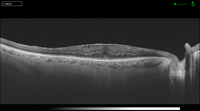

Figura 8. Pseudoagujero con membrana epiretiniana.

Figura 9. Membrana epiretiniana con engrosamiento macular.

Figura 10. Membrana epiretiniana con tracción foveolar, perdiendo su perfil natural.